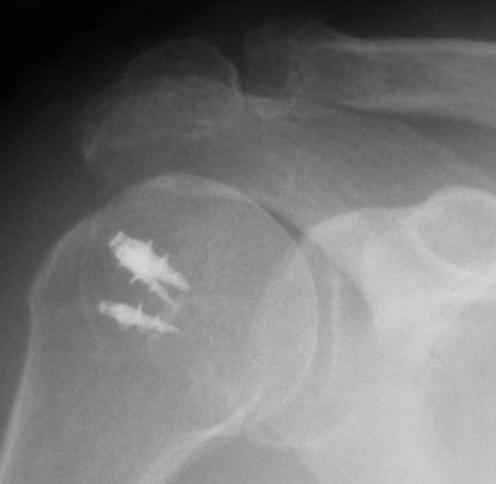

Физический активный мужчина 50 лет в мае 2009 года был оперирован на правом плечевом суставе. Выполнялся открытый шов надостной мышцы и субакромиальная декомпрессия по поводу ее частичного разрыва и импиджмент синдрома III степени. Послеоперационный период протекал без осложнений. Гипсовая иммобилизация в положении отведения плеча до 45 градусов в течение 6 недель.В последующем, несмотря на активные занатия ЛФК, сформировалась приводяще-внутриротационная контрактура оперированного сустава (отведение до 80 градусов, наружная ротация до 15 градусов. Болевого синдрома нет, при пассивном отведении плеча создается впечатление "механического" препятствия движению.На контрольных рентгенограммах складывается впечатление о сформировавшемсся верхнем подвивихе головки правой плечевой кости, как о причине контрактуры. Хотелось бы услышать мнение коллег о такттике дальнейшего лечения.

В качестве примера - снимки до и после восстановления целостности вращательной манжеты после 3-хмесячной давности полного разрыва. Видно, что верхний подвывих устранен.